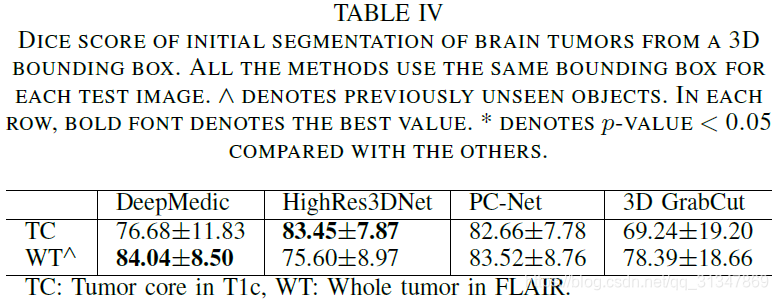

(1)PC-Net 实现的初始分割结果与其他方法的对比:

从下表看出,DeepMedic 在 T1c 上的准确率比较低,在 FLAIR 上的准确率较高,HighRes3DNet 刚好和它相反。